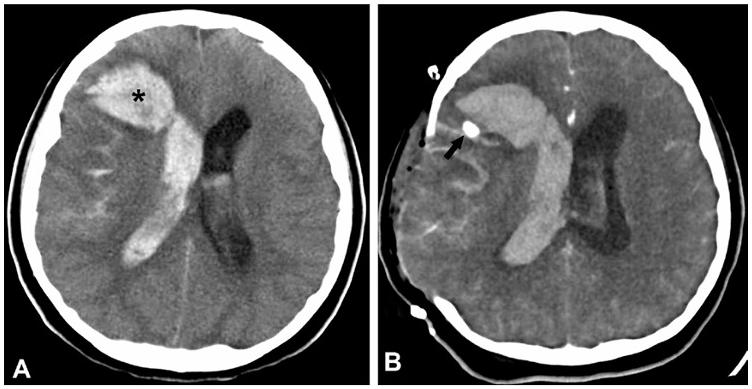

2. Angiografia nella malattia di Moyamoya; appare evidente un restringimento significativo della carotide interna e la presenza caratteristica dei collaterali “a nuvola di fumo” con perfusione corticale ridotta.

Alla TC invece le lesioni ischemiche sono visibili dopo circa 24 ore sottoforma di zone ipointense; i trombi risultano evidenti come aree iperdense così come il versamento ematico, che

generalmente presenta una forma irregolare e un effetto compressivo sui tessuti circostanti [Figure 5,6].

Figura 5. Immagine 1: RMN di stroke ischemico arterioso. A: ampia regione iperintensa in DWI compatibile con un infarto nel territorio dell’MCA sinistra (frecce nere). B: assenza del normale segnale di flusso a carico del medesimo territorio vascolare in angiografia (asterisco bianco). Immagine 2: RMN di trombosi venosa cerebrale. A: segnale iperintenso in T1 nel seno sagittale superiore (frecce bianche). B: segno del delta vuoto del seno sagittale superiore che delinea un trombo triangolare in una sequenza T1 con contrasto (frecce bianche).

Figura 6. Immagine TC (veduta assiale) di aneurisma rotto. A: ematoma intraparenchimale frontale destro (asterisco nero) con estensione di sangue nel ventricolo laterale destro e presenza di emorragia subaracnoidea. B: la somministrazione di mezzo di contrasto evidenzia un aneurisma (freccia nera) immediatamente posteriore all’ematoma. Si noti l’esecuzione di una craniotomia decompressiva.